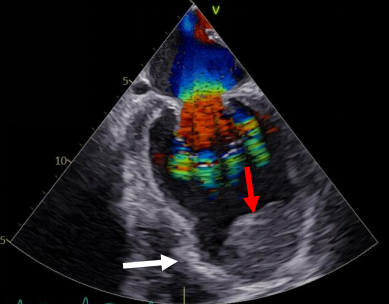

此次就诊,张主任发现患者心脏超声检查显示左心室射血分数仅有30%,同时存在巨大室壁瘤和左心室附壁血栓(图1)。患者年纪轻轻便出现心肌梗死,是不是因卵圆孔未闭引起矛盾性血栓栓塞所致?此外患者存在慢性肺栓塞,如果存在卵圆孔未闭,若下次出现矛盾性血栓栓塞,则有可能发展成脑梗死。于是张主任决定行发泡试验和经食道超声检查,结果证实了张主任的猜想,患者明确存在卵圆孔未闭。

(图1)术前超声心动图提示心尖部可见巨大室壁瘤(白色箭头),其内可见巨大附壁血栓(红色箭头)。